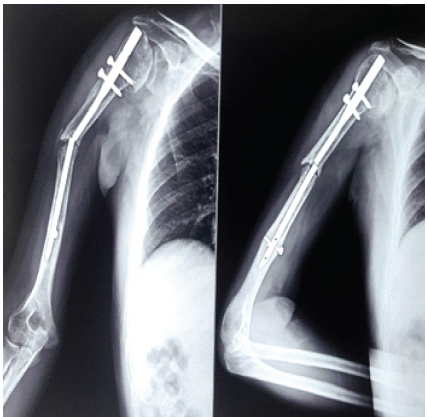

In May 2025, he developed insidious-onset pain and progressive difficulty in using the affected limb without any preceding history of trauma or fall. He also reported having undergone pacemaker implantation 3 months before presentation for a cardiac indication. On clinical examination, there was localized tenderness over the right mid-arm region with restriction of shoulder and elbow movements secondary to pain, raising suspicion of implant failure and non-union, which was subsequently confirmed on imaging studies.

Radiological evaluation revealed a non-union of the right mid-diaphyseal humerus associated with non-traumatic breakage of the IMIL nail. All routine pre-operative investigations were within normal limits (Fig. 3).

Figure 3: Current (May 2025) anteroposterior and lateral radiographs of the right humerus showing established mid-diaphyseal non-union with implant failure due to breakage of the intramedullary interlocking nail.